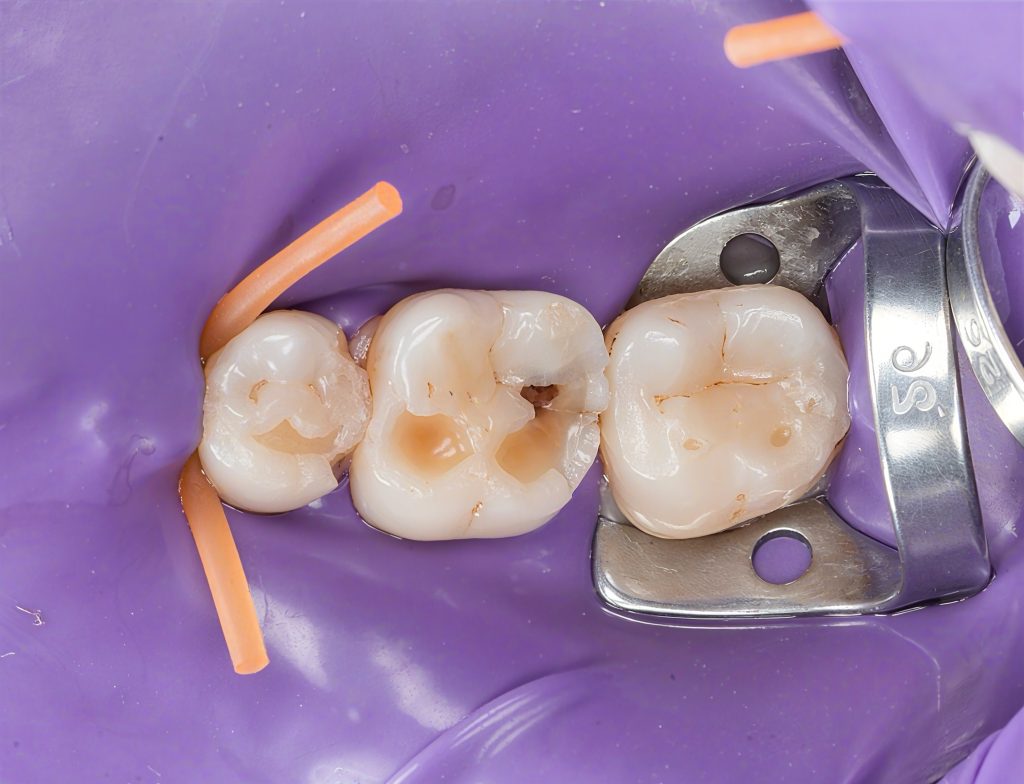

Clinical Pictures (Isolation & Access)

Image 3:

“Initial clinical presentation showing occlusal fissure staining, marginal breakdown and early proximal cavitation.”